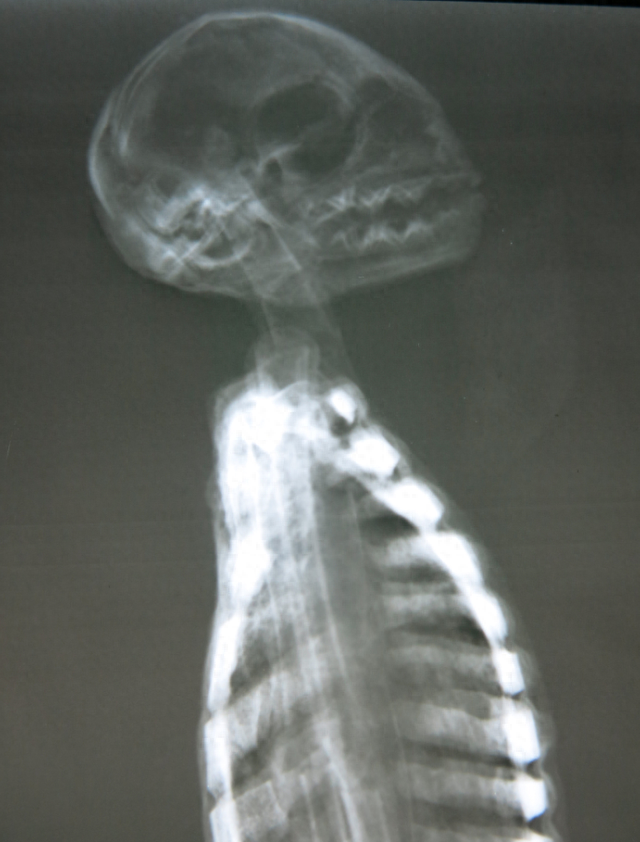

▲外星人木乃伊的头骨显然取自其他动物

按照莫桑的说法,这些“外星人木乃伊”存在完整的内部构造,但经过X光照射分析,这些所谓的外星人全都是粗制滥造的假货。事实上,所谓的木乃伊确实存在“骨骼结构”,但明显不是自然生长的,而是用人和动物的骨骼拼装而成的。脊柱、肋骨和肢体全部都是用折断的鸟类骨骼拼在一起的,而且没有任何关节相互连接。其中一个代号“E.V.”的木乃伊头骨取自某种小型动物,另一些外星人的头骨则取自猴子和美洲驼。

▲这个头骨取自美洲驼的后脑